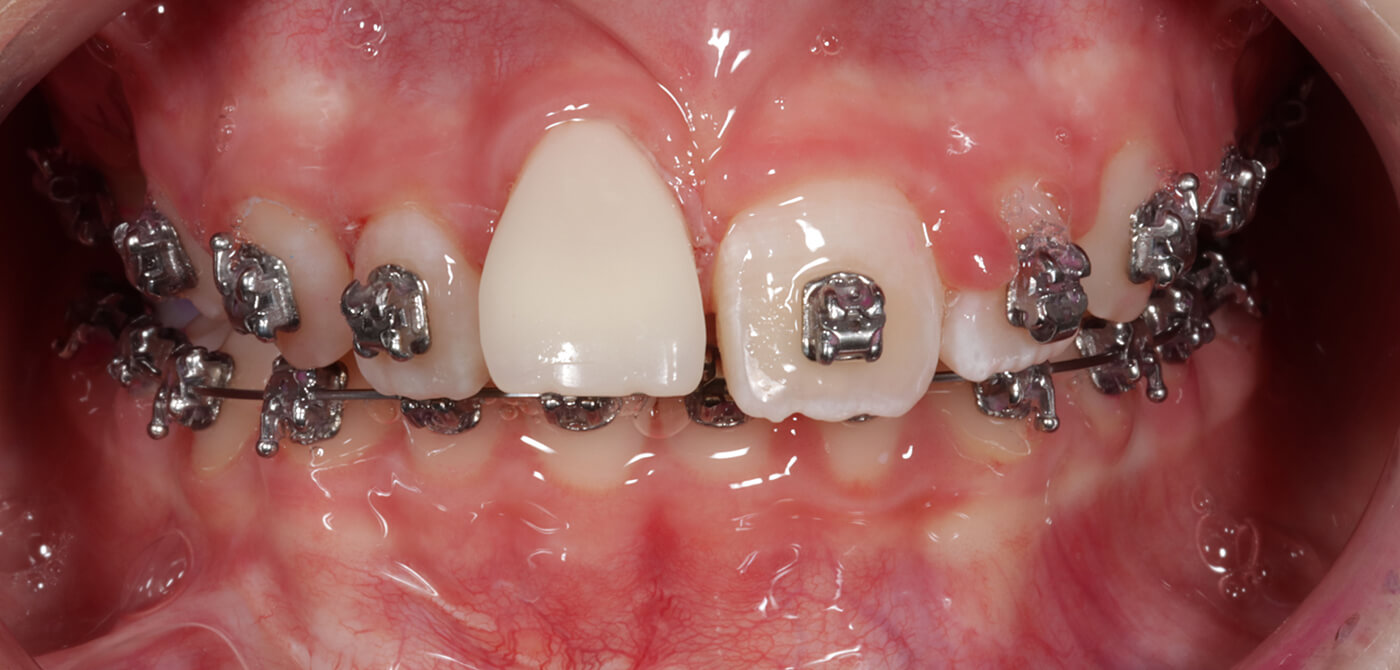

Situatie na tandopbouw (foto door Proclin)

De behandeling voerden we uit in nauwe samenwerking met Proclin in Rotterdam. Ortho Fleur begeleidde het orthodontische deel van de behandeling, terwijl de autotransplantatie zelf werd uitgevoerd door dr. D.S. Barendregt van Proclin. Om de verplaatste kies zoveel mogelijk op een voortand te laten lijken, is deze door Proclin zorgvuldig opgebouwd met vulmateriaal.